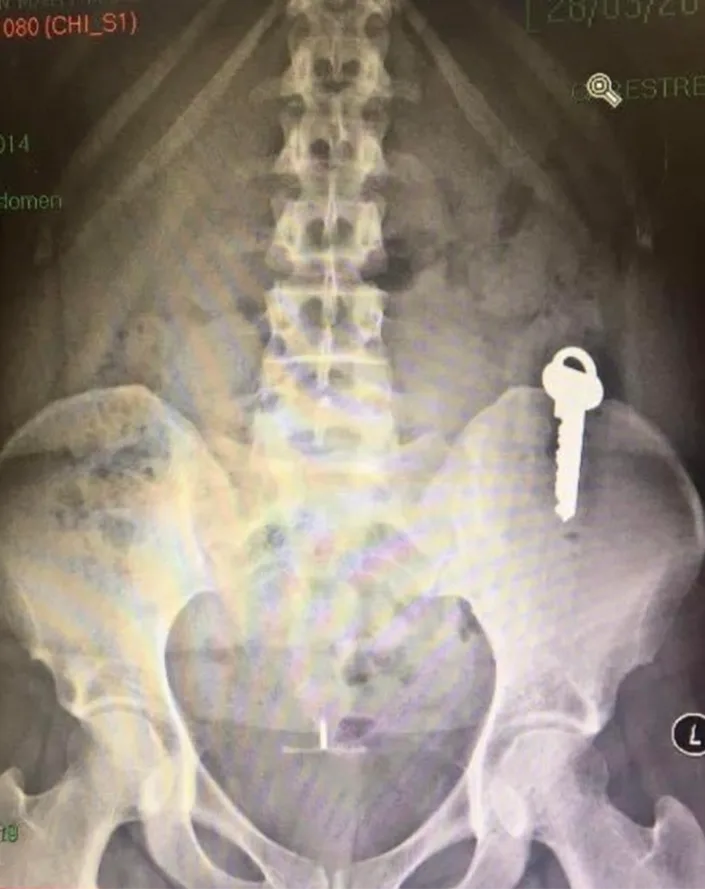

According to The Sun, doctors carried out an x-ray which revealed the key was logged in Siobhan’s large intestine. Luckily, she was told there wasn’t any risk and the key would simply pass naturally, which it did 5 days later.